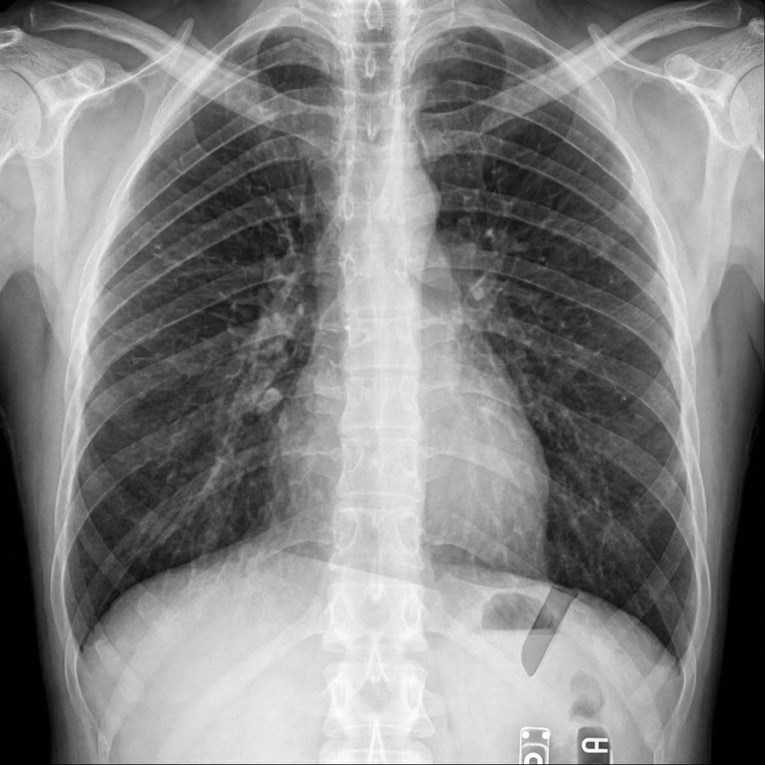

Nakon vađenja umnjaka počeo čudno štucati, rendgen otkrio uzrok